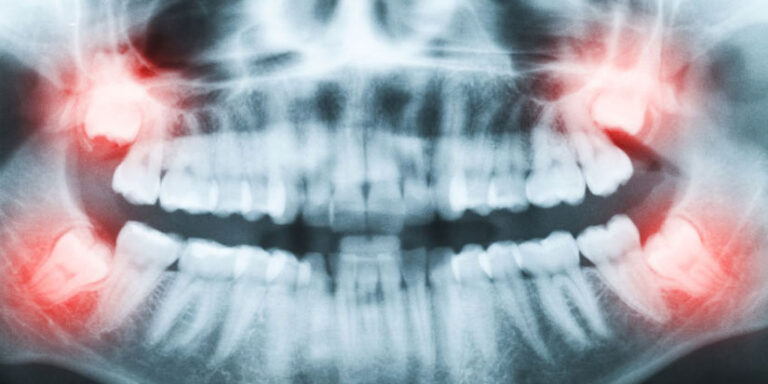

Explore a full range of advanced oral surgery procedures designed to restore health, function, and confidence. Our board-certified Oral and Maxillofacial Surgeons provide expert care in dental implants, wisdom teeth removal, tooth extractions, bone grafting, and sedation anesthesia. Using state-of-the-art technology and a patient-first approach, every procedure is performed with precision and comfort in mind. Whether you need a single treatment or comprehensive surgical care, our team is committed to delivering safe, effective solutions tailored to your needs and long-term oral health goals.